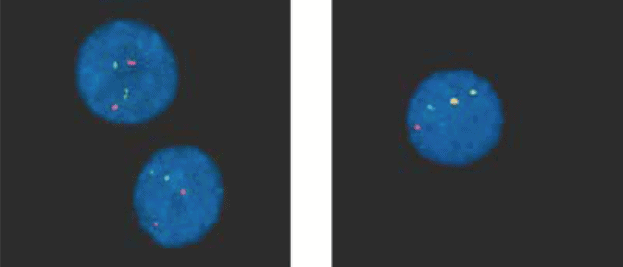

FISH é um exame laboratorial usado para examinar genes e cromossomos nas células. O FISH é um método mais sensível para detectar o cromossomo Ph do que testes normais de citogenética e pode identificar a presença do gene BCR-ABL (veja figura 4). No caso da LMC, o FISH usa sondas de cor que se ligam a segmentos específicos do DNA dos genes BCR e ABL nos cromossomos. Os genes BCR e ABL são marcados com diferentes substâncias químicas, cada uma das quais libera uma cor diferente, permitindo sua identificação. A cor aparece no cromossomo que contém o gene, isto é, no cromossomo 9 para ABL e no cromossomo 22 para BCR e, portanto, pode detectar o pedaço do cromossomo 9 que se moveu para o cromossomo 22 nas células de LMC. A fusão do gene BCR-ABL é mostrada pela sobreposição de cores nas duas sondas. A figura abaixo mostra o momento em que o Gene BCR-ABL está sendo identificado nas células, usando o FISH.

Hibridização in situ fluorescente, ou FISH, é um método de teste que usa moléculas fluorescentes para marcar o gene BCR-ABL na LMC. Nas células normais, dois sinais vermelhos e dois verdes indicam a localização normal do gene ABL e BCR, respectivamente. Nas células anormais, a fusão BCR-ABL é visualizada por meio da fusão dos sinais verde e vermelho. É frequentemente detectado como amarelo fluorescente (mostrado por setas).